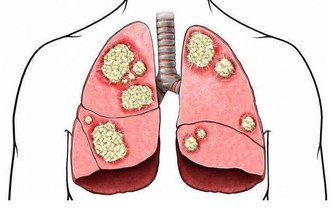

在按壓腹部時,患者會明顯的感覺疼痛,而且也會有包塊的存在。這是腫瘤跟周圍的組織粘在一起形成的腫塊,而且這些腫塊會活動。在檢查B超時,會發現腫塊的大小不規則,尤其是到了晚期,腫塊會不斷增大,變得不再活動。

總而言之,腸癌對人體健康的影響是很大的,屬於惡性腫瘤。若平時感覺到身體不適,經常的出現便血,必須要合理的進行檢查。如果出現腸癌,也不要氣餒,不要放棄治療。在早期時,疾病可以有效控制,患者需選擇適合的治療方法,有效的緩解疼痛。千萬不要坐以待斃,放棄治療。